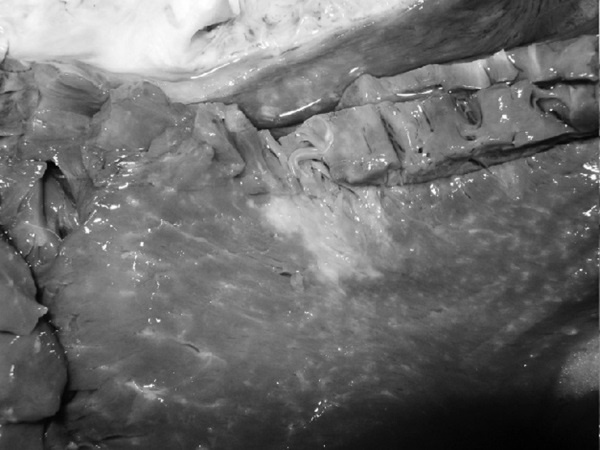

Рис. 1. Результаты аутопсии больного 68 лет

В рамках академической книги, естественно, следует выдерживать определенный стиль изложения, хотя каждому понятно, что на протяжении 12 лет практически помощи пациенту не было. Но тем не менее давайте вместе проанализируем факты, так как они изложены в амбулаторной карте. Итак, начнем с диагноза ИБС, после которого вместо определения клинической ее формы (постинфарктный кардиосклероз, хроническая аневризма и т. д.) доктор пишет морфологический диагноз: атеросклероз коронарных сосудов. В клинике этот диагноз может быть выставлен только при условии имеющейся коронарографии. Далее за 12 лет нет информации об ЭКГ, нарушениях ритма и пр. Поэтому и форму ИБС установить затруднительно, уже не говоря об отсутствии за столько времени ЭХОКГ. Но тем не менее диагноз был выставлен, были все показания для назначения обоснованной терапии. Ни обоснований, ни самой терапии в амбулаторной карте нет. В 2003 году пациент переносит ОНМК, после чего ему назначают курсами винпоцетин и пирацетам. Трудно комментировать эти назначения, поскольку нет не только доказательной базы эффективности указанных препаратов, но и обоснованных рекомендаций по их применению у больных после перенесенного инсульта. Далее с 2004 по 2007 год единичные осмотры терапевта и невролога по поводу жалоб на слабость в конечностях, головокружения и снижение памяти. Указания на иммобилизацию отсутствуют. Очевидно, что отсутствие наблюдения, медикаментозной и реабилитационной поддержки, а как вы узнаете и позже – отсутствие понимания значения маломобильности превратило существование пациента только в одно – самостоятельную борьбу за жизнь. Эта борьба была продолжена еще в течение 4 лет. Случайным осмотром отмечены трофические нарушения и отечность нижних конечностей, пролежни, снижение памяти и плохой сон. Интерпретации клинической дано не было, судить о причине отеков (сердечная недостаточность или местные кожные или сосудистые изменения) невозможно. Цифры АД не указаны (!). Но тем не менее был выставлен диагноз, в котором впервые прозвучала токсическая полиневропатия (что имелось в виду и какой токсикоз, осталось за кадром клинических мыслей врача), НК 1 и пролежни. Выписан феназепам по 0,5 мг на ночь (обещали придерживаться академизма, но выдержать сложно, цинизм в худшем его проявлении). Следующая запись через 2 месяца – констатация смерти. 68-летний пациент после смерти даже «не заслужил» посмертного эпикриза. По данным секции, у больного был очень высокий кардиоваскулярный риск (табл. 1), определяемый мультифокальным атеросклерозом, АГ и ХБП.